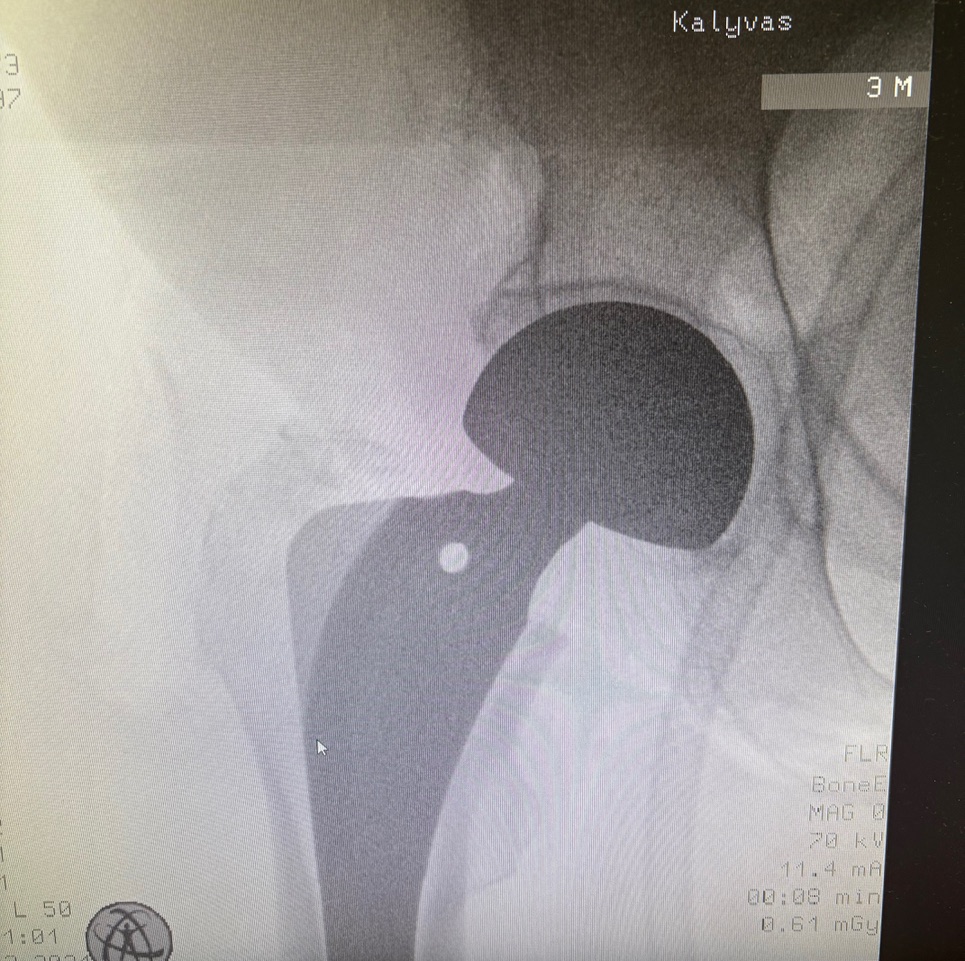

Η ημιολική αρθροπλαστική ισχίου με την ελάχιστα επεμβατική τεχνική AMIS (Anterior Minimally Invasive Surgery) αποτελεί σύγχρονη χειρουργική επιλογή. Η επέμβαση πραγματοποιείται από πρόσθια προσπέλαση, χωρίς διατομή μυών, γεγονός που συμβάλλει σε μικρότερο μετεγχειρητικό πόνο, ταχύτερη αποκατάσταση και άμεση κινητοποίηση του ασθενούς. Η τεχνική AMIS επιτρέπει υψηλή ακρίβεια τοποθέτησης της πρόθεσης και μειώνει τον κίνδυνο εξαρθρήματος, προσφέροντας ασφαλή και αξιόπιστα λειτουργικά αποτελέσματα.

Ο έμπειρος ορθοπαιδικός χειρουργός κ. Νικόλαος Καλύβας εφαρμόζει την Ημιολική Αρθροπλαστική Ισχίου με τεχνική (AMIS) επί σειρά ετών στη Γερμανία, έχοντας χειρουργήσει μεγάλο αριθμό ασθενών. Τα τελευταία χρόνια, από τη θέση του Αναπληρωτή Διευθυντή σε ένα από τα μεγαλύτερα κέντρα αρθροπλαστικής της Γερμανίας, είχε ενεργό ρόλο στην εκπαίδευση ειδικευομένων ορθοπαιδικών στη συγκεκριμένη τεχνική.